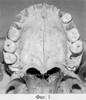

На фиг.1 представлена фотография костей твердого неба в норме; на фиг.2 изображена схема уровня среза черепа в аксиальной проекции под углом, соответствующим пунктирной линии; на фиг.3 изображена схема горизонтальной плоскости твердого неба и крючков крыловидных отростков клиновидной кости с проведенными измерениями; на фиг.4 представлена боковая топограмма черепа с отмеченным линией уровнем среза; на фиг.5 представлена томограмма горизонтальной плоскости твердого неба и крючков крыловидных отростков клиновидной кости с проведенными планиметрическими измерениями.

В норме задняя носовая ость (spina nasalis posterior- место прикрепления небного апоневроза и мышцы язычка (m. uvulae)) в горизонтальной плоскости находится на уровне крючков крыловидных отростков клиновидной кости (hamulus pterygoideus) (фиг.1). При наличии у пациента любой формы расщелины неба имеется недоразвитие, и вследствие этого укорочение твердого неба той или иной степени. При наличии полной односторонней или двусторонней расщелины неба задняя носовая ость (spina nasalis posterior) отсутствует, костные фрагменты горизонтальной пластинки небной кости (Lamina horizontalis os palatinum) значительно недоразвиты и укорочены. За счет этого отмечается продольное укорочение горизонтальной плоскости твердого неба. Расстояние от уровня задневнутренних углов фрагментов горизонтальной небной пластинки до уровня линии, проведенной от одного крючка крыловидного отростка клиновидной кости до другого, является величиной укорочения горизонтальной плоскости твердого неба. Наличие укорочения горизонтальной плоскости твердого неба при врожденной расщелине является главной причиной возникновения деформации и сморщивания мягкого неба в послеоперационном периоде, что приводит к небно-глоточной недостаточности. В связи с этим очень важно определить перед операцией укорочение твердого неба объективно в точном цифровом варианте.